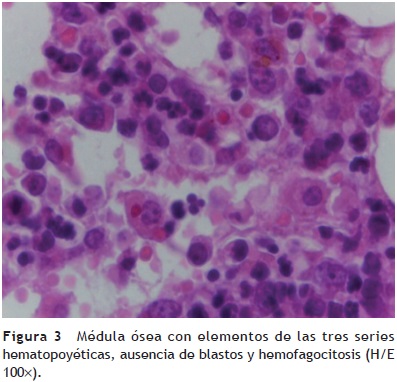

Médula ósea. Se observaron trabéculas óseas con revestimiento de osteoblastos, y las celdillas ocupadas por las tres series hematopoyéticas. La relación de la celularidad de la médula ósea con respecto al tejido adiposo es del 50 al 60%. Cuando se observa la celularidad a mayor aumento, se aprecia que hay elementos principalmente de la serie mieloide, con granulocitos y maduración hasta bandas. También se observa la presencia de megacariocitos, y escasos elementos de la serie eritroide. Cabe mencionar que no hay presencia de blastos. Otro hallazgo importante es la hemorragia reciente y el depósito de hemosiderina. Es importante mencionar la presencia de los megacariocitos, pues es la primera serie que desaparece ante la presencia de leucemia. En este momento está recuperada la médula. Con un objetivo de 100× podemos ver la presencia de histiocitos con eritrocitos en su citoplasma. Esta hemofagocitosis es secundaria, tanto al proceso neoplásico como al tratamiento y a la evolución de esta paciente (fig. 3).

Los diagnósticos post mortem de la médula ósea fueron los siguientes:

• Médula ósea en remisión, sin presencia de blastos, con presencia de hemosiderosis, hemofagocitosis y de las tres series hematopoyéticas con maduración normal.